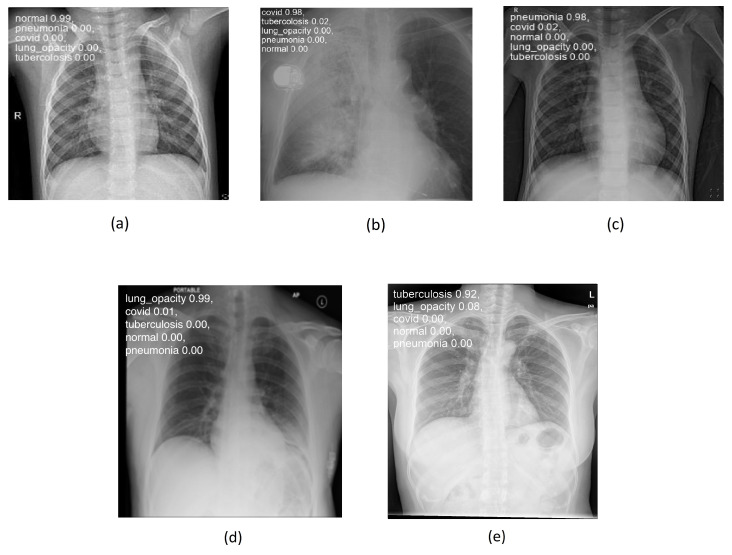

Figure 4a–e below illustrate the “normal”, “covid”, “lung_opacity”, “pneumonia”, and “tuberculosis” classes.

Figure 4.

Chest images for (a) “normal”, (b) “covid”, (c) “pneumonia”, (d) “lung_opacity”, and (e) “tuberculosis” classes.

Figure 8 shows some examples of lung images, each corresponding to its respective pathology, with the classification percentage result for all classes. As can be observed, the model performs very well even on images it has never seen before, achieving a rate of accuracy ranging from 92 to 99%.

Figure 8.

Lung disease classification for (a) “normal”, (b) “covid”, (c) “pneumonia”, (d) “lung_opacity”, and (e) “tuberculosis” classes using testing set.